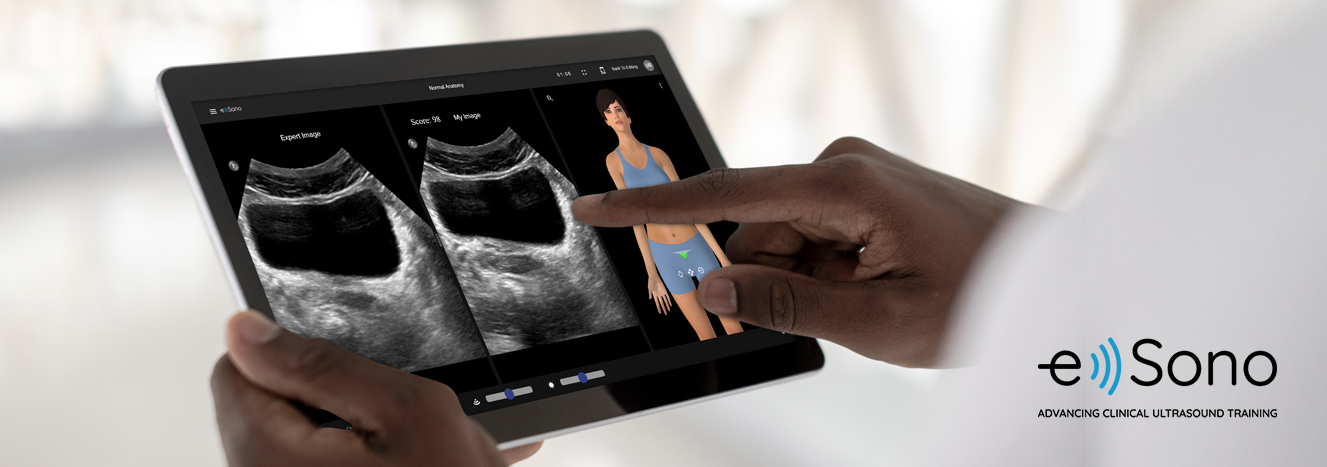

Раздел: Галерея прозрений